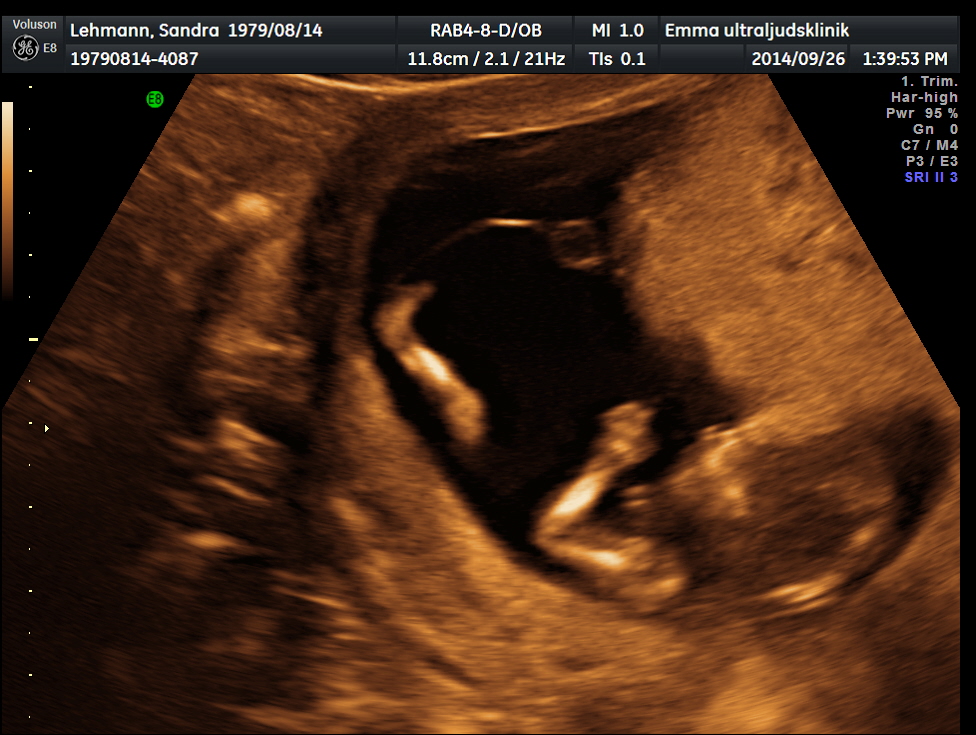

Ultraljudet var så spännande, och bilderna man fick. Man tittade sönder dem. Nu först tog jag upp bilderna och tittade på dem. Och vi var på ultraljudet för 6 veckor sedan.